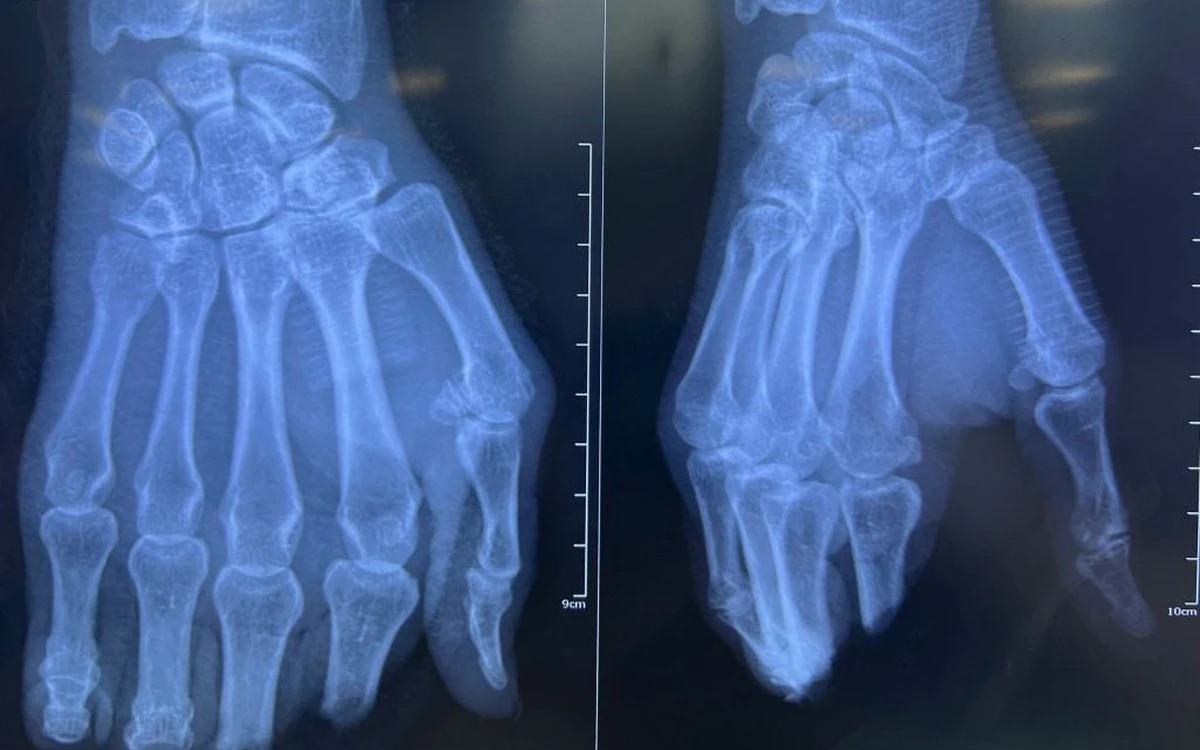

| 8 tiếng phẫu thuật nối 4 ngón tay đứt lìa | |

| Trong lúc cắt giấy, một bệnh nhân nam đã bị cắt đứt lìa hoàn toàn 4 ngón tay, may mắn được các bác sĩ Bệnh viện Nhân dân 115 (TP.HCM) nối kịp thời....Xem tiếp>>> | |

- 8 tiếng phẫu thuật nối 4 ngón tay đứt lìa 1 giờ trước